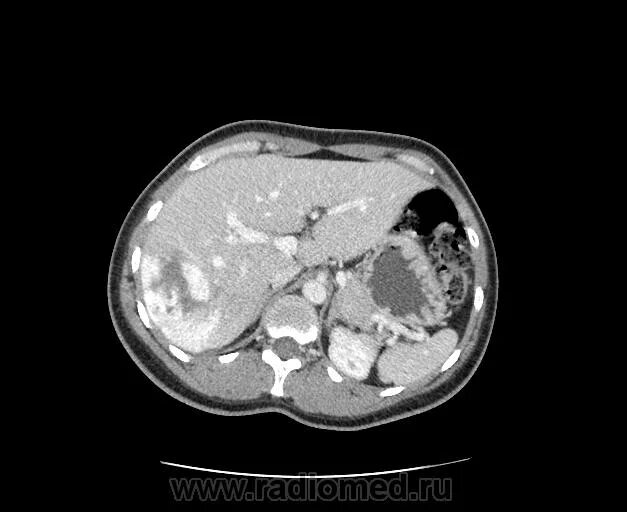

Эмболизация гемангиомы